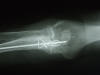

Fractura supracondílea de codo.

Fractura supracondílea de codo.Tras reducción y osteosíntesis.

Fractura supracondílea de codo. Tratamiento con agujas.